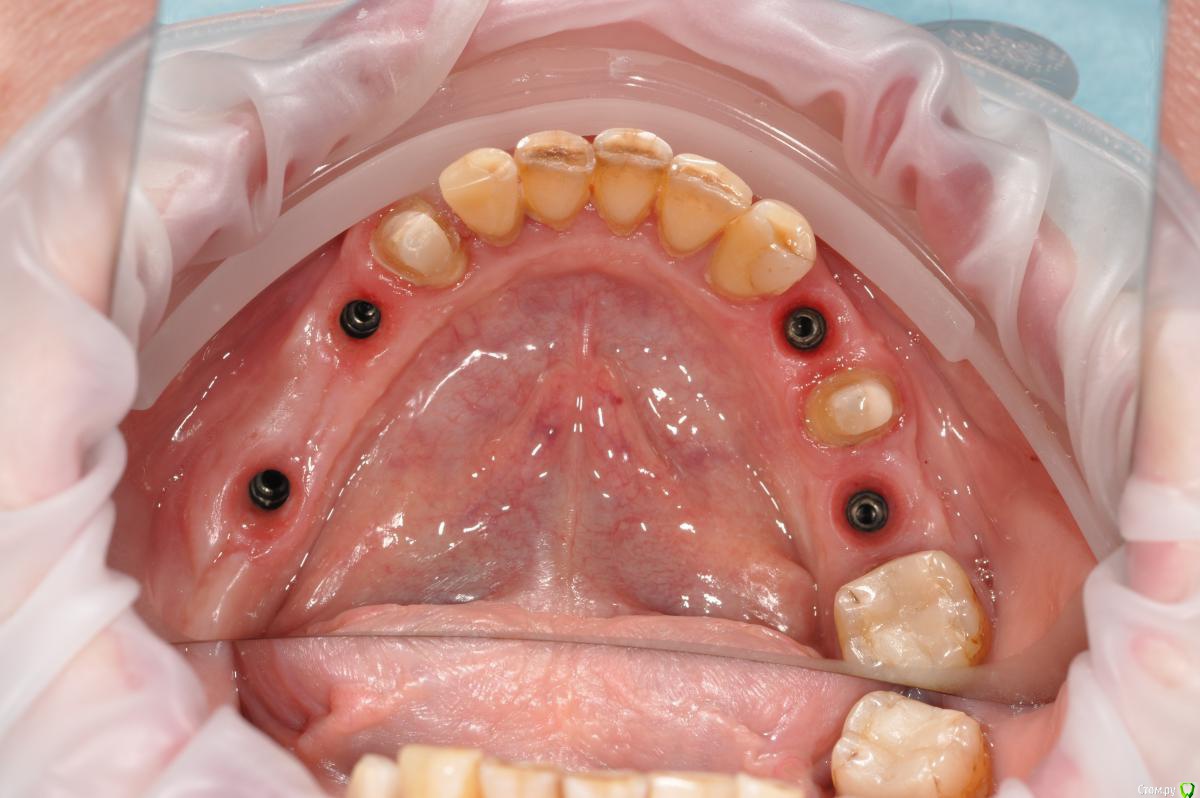

Neilrus Опубликовано 16 ноября, 2018 Поделиться Опубликовано 16 ноября, 2018 Отсеки слизистую и подшей ниже будто сдт собираешься подсадить. С подворотом. Из сом сделай гребень. Клеить и к фдм и к зубам рядом если есть. Надо фото найти... Господа, Как вы решаете вопрос с отсутствием зкпд в полном обьеме.у пациенки жалобы на то что" при поднятии языка, дна полости рта поднимается и нализиет на формирователь десны, соответственно на протезирование я пока не хочу передавать.в течении 3 недель у пациентки выросла шишка под языком в области 3 6 зуба...убрал формирователь и поставил заглушку.Видел у Ильгама как он делал зкпд, не скинете видео? не могу найтии что делать с этой шишкой и как вести пациента? спасибодумаю до надкостницы расщепитесь со стороный переходной, подшейте как можно ниже, а к самой надкостнице полнослойный как можно плотнее пришейте, без фдм будет лучше, их потом, Каппу не забудьте на небо заранее, ибо кусочек будет нормальный.Почти похожий случай, фоткиприкрепил, не судите строго, выкладываюсь редко, прикрепленки было 1,5-2мм и то язычно 2 Ссылка на комментарий

Neilrus Опубликовано 16 ноября, 2018 Поделиться Опубликовано 16 ноября, 2018 (изменено) что-то они в обратно порядке залились..ваще опыта нет (конец вот такой: Изменено 16 ноября, 2018 пользователем Neilrus Ссылка на комментарий

kamranchick Опубликовано 17 ноября, 2018 Автор Поделиться Опубликовано 17 ноября, 2018 думаю до надкостницы расщепитесь со стороный переходной, подшейте как можно ниже, а к самой надкостнице полнослойный как можно плотнее пришейте, без фдм будет лучше, их потом, Каппу не забудьте на небо заранее, ибо кусочек будет нормальный.Почти похожий случай, фоткиприкрепил, не судите строго, выкладываюсь редко, прикрепленки было 1,5-2мм и то язычнону у вас ситуация понятная.... не такая тяжелая, а тут вообще ее нет, даже если бы была язычно 1.5 мм. было бы намного проще. она бы на месте оставалась бы при движении языком туда сюда, в моем случае, любое движение языком это катастрофа Ссылка на комментарий